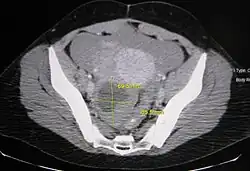

| A simple ovarian cyst of most likely follicular origin | |

Ovarian cysts are usually diagnosed by pelvic ultrasound, CT scan, or MRI, and correlated with clinical presentation and endocrinologic tests as appropriate.[15] Ultrasound is the most important imaging modality, as abnormalities seen in a CT scan sometimes prove to be normal in ultrasound.[5][8] If a different modality is needed, then MRIs are more reliable than CT scans.[5]